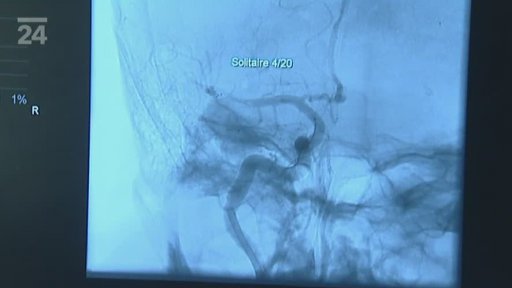

Cévní mozková příhoda neboli mozkový infarkt - jedno z nejzávažnějších onemocnění vůbec. Je druhou nejčastější příčinou smrti a nejčastějším viníkem těžkého postižení u seniorů. Mozková mrtvice ale postihuje i stále mladší lidi ? proto se lékaři snaží vyvíjet nové léčebné postupy. Novinkou posledních let je využití ultrazvuku přímo k léčbě a k prevenci. Jak zvyšuje šance pacientů na uzdravení, zkoumají neurologové v ostravské fakultní nemocnici.

Hra o čas - někdo se bojí, někdo o tom vtipkuje, někdo si říká, že ho to snad mine. Zásadní ale je, co člověk udělá, když zpozoruje příznaky u sebe nebo u někoho jiného. Největší šanci mají pacienti, kteří se dostanou do nemocnice do 90 minut, hranicí je pak 9 hodin. Příběhy 51letého muže nebo 27 ženy, matky novorozeněte, ukazují, jak dokáže mozková příhoda změnit život a jakou roli v tom sehrává špičková léčba i další faktory.

Neurolog Robert Mikulík - medicína nebyla přímo jeho snem, zlákal ho ale vývoj techniky a naděje, kterou to přináší nemocným. Je uznávaným odborníkem v léčbě mozkové mrtvice, pomáhal prosadit trombolýzu, je spolutvůrcem projektu Mezinárodního centra klinických výzkumů v Brně (ICRC). Působí ve FN u svaté Anny v Brně, pracoval ale i ve USA a jeho srovnání českého a amerického zdravotnictví byste si neměli nechat ujít.